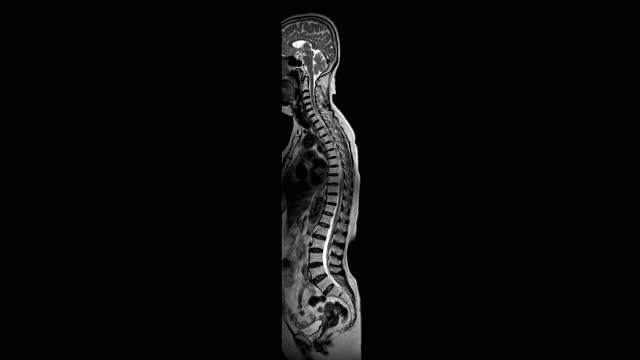

척추관협착증은 척추 주변의 근육과 인대가 퇴행하여 척추관 내 황색 인대가 비정상적으로 부풀어 오르면서 발생하는 퇴행성 척추질환 중 하나입니다. 이 질환은 가까운 거리도 통증으로 인해 걷기가 어려워지는 특징을 가지고 있으며, 새벽에 다리에 통증을 느끼는 경우가 많습니다.